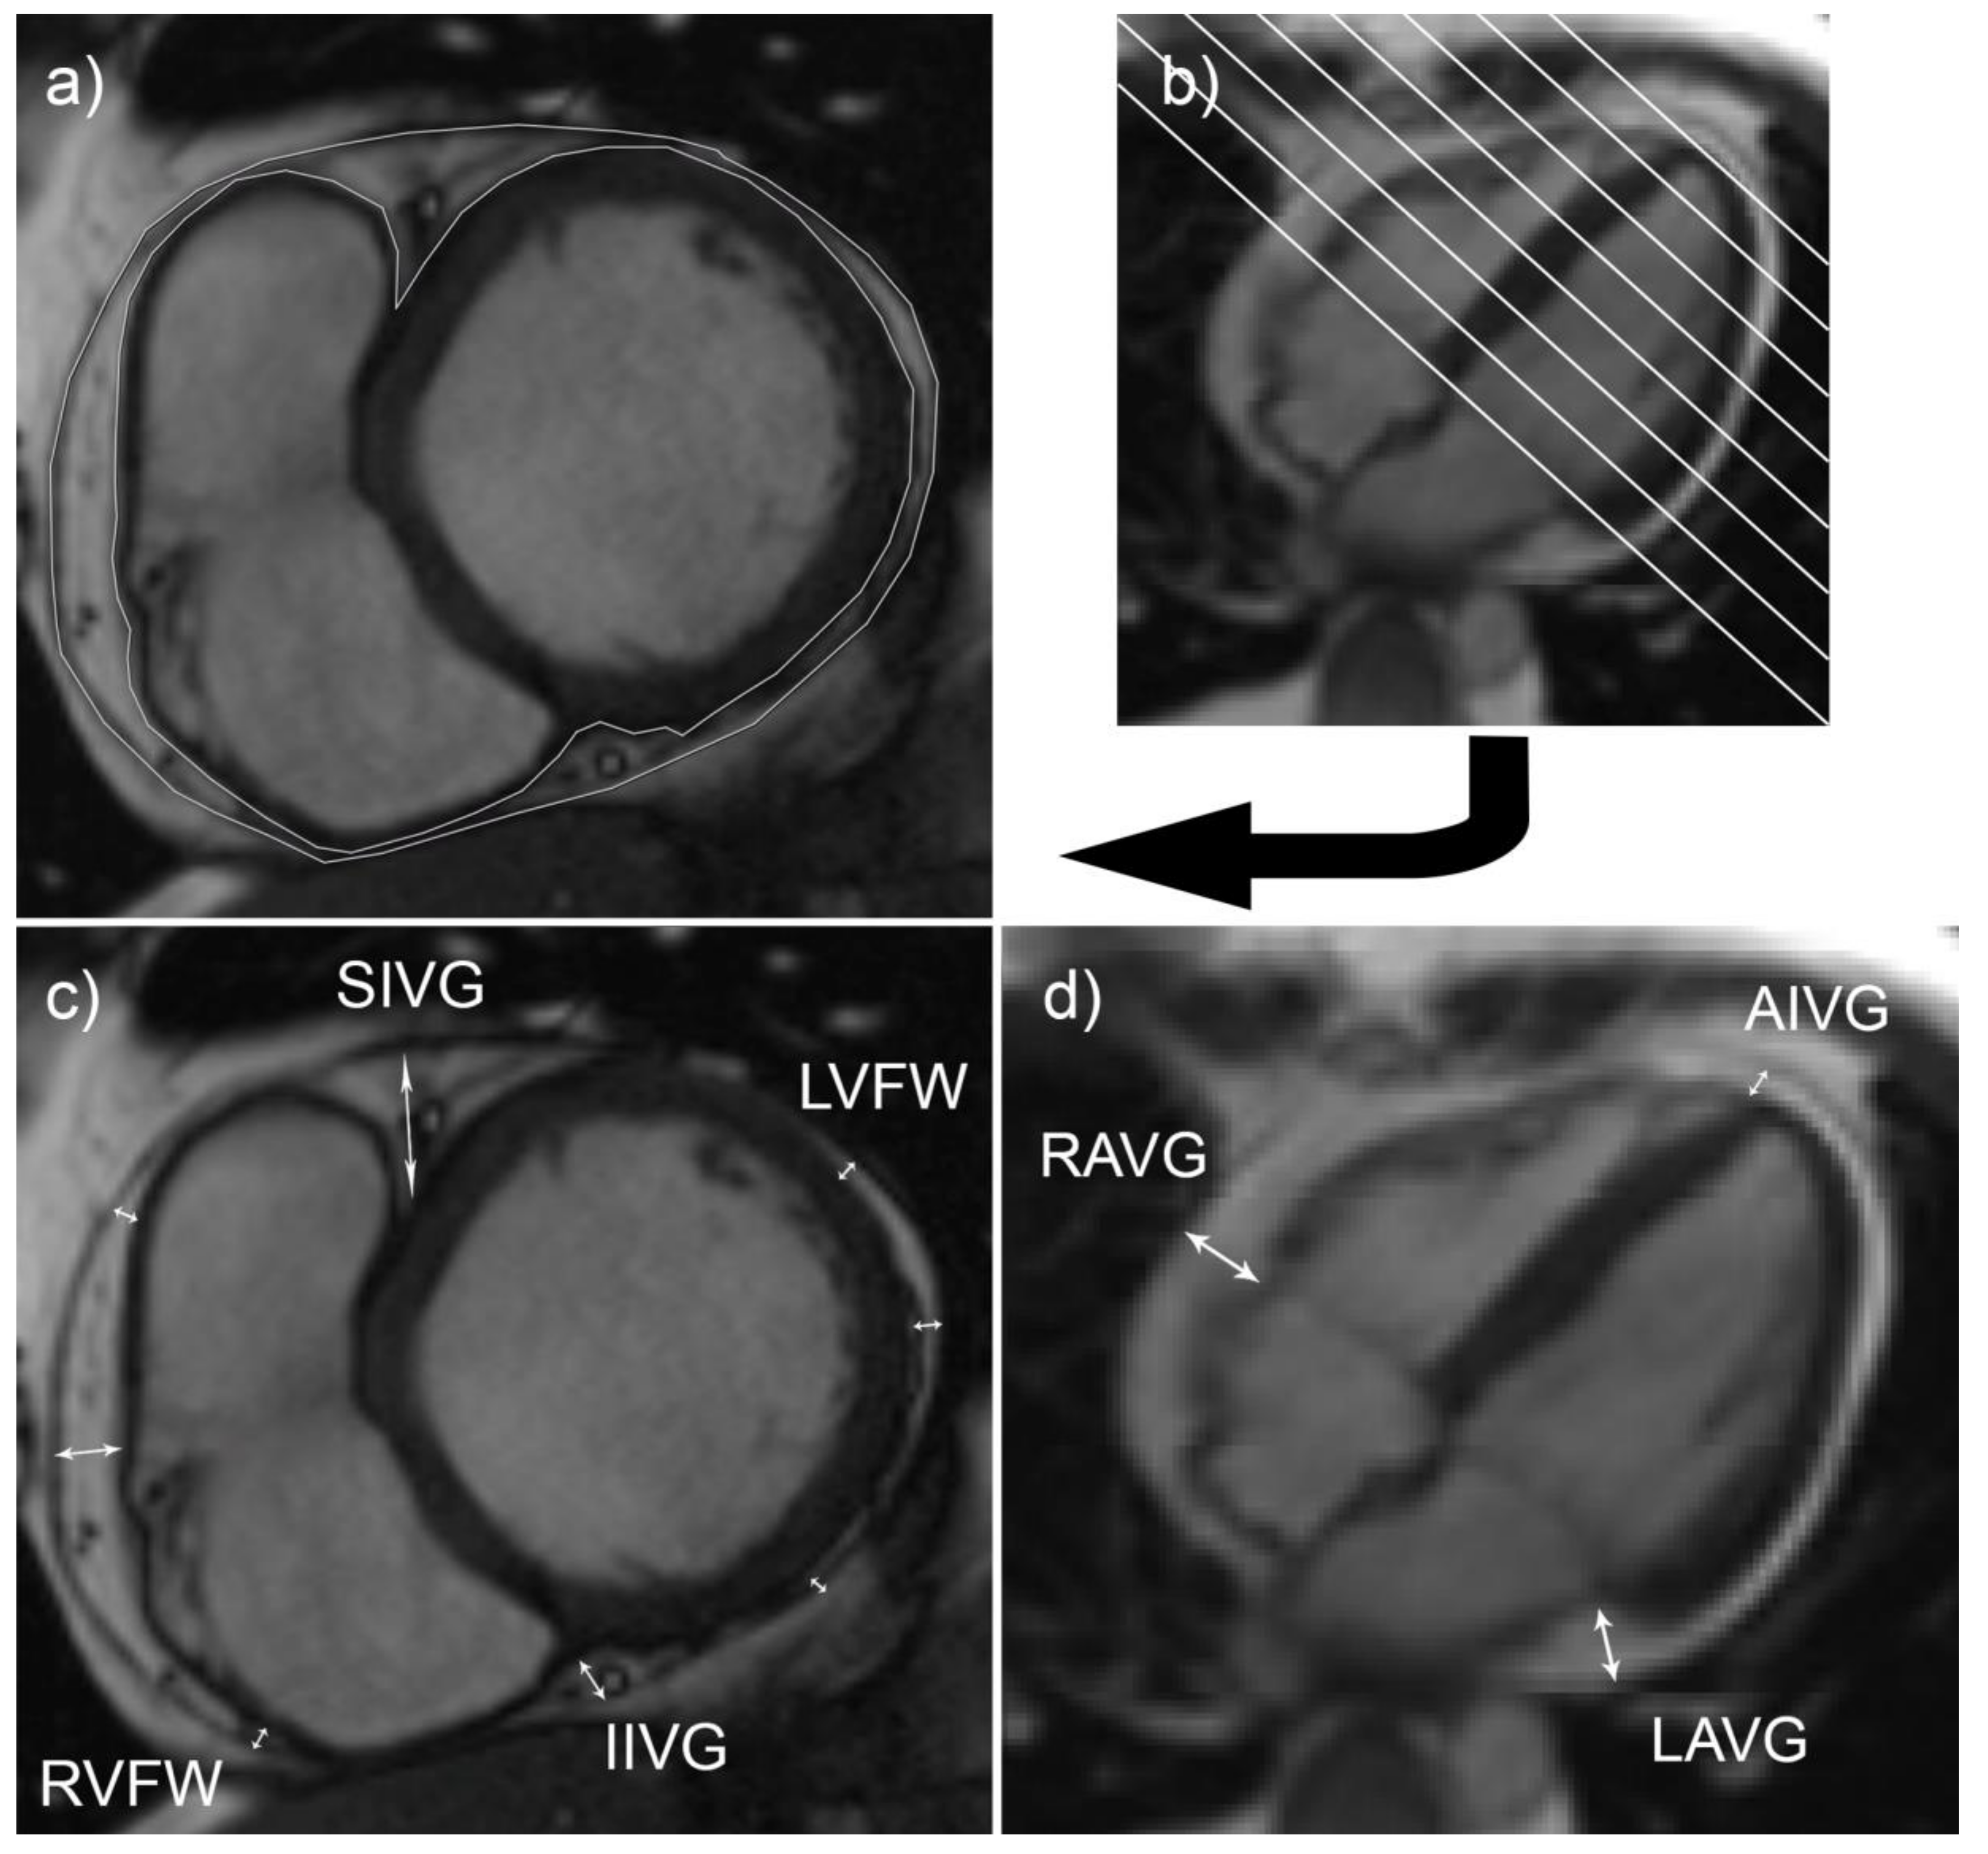

2.3. Assessment of the Size of Epicardial Adipose Tissue Depots